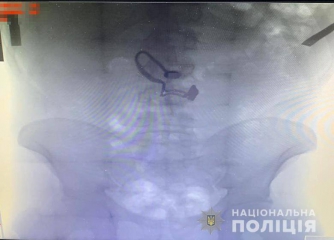

В Киеве прохожие помогли полиции задержать мужчину, который после ограбления проглотил цепочку потерпевшей.

Злоумышленник сорвал с шеи женщины украшение и отобрал у нее кошелек с деньгами. Это увидели прохожие, догнали его и вызвали полицию.